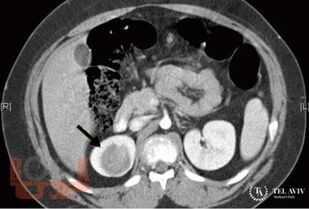

В учебном пособии представлены современные взгляды на злокачественные новообразования детского возраста, такие как нефробластома, нейробластома, опухоли печени, экстракраниальные герминогенно-клеточные опухоли; обсуждаются вопросы классификации детского рака, основные принципы диагностики злокачественных новообразований.